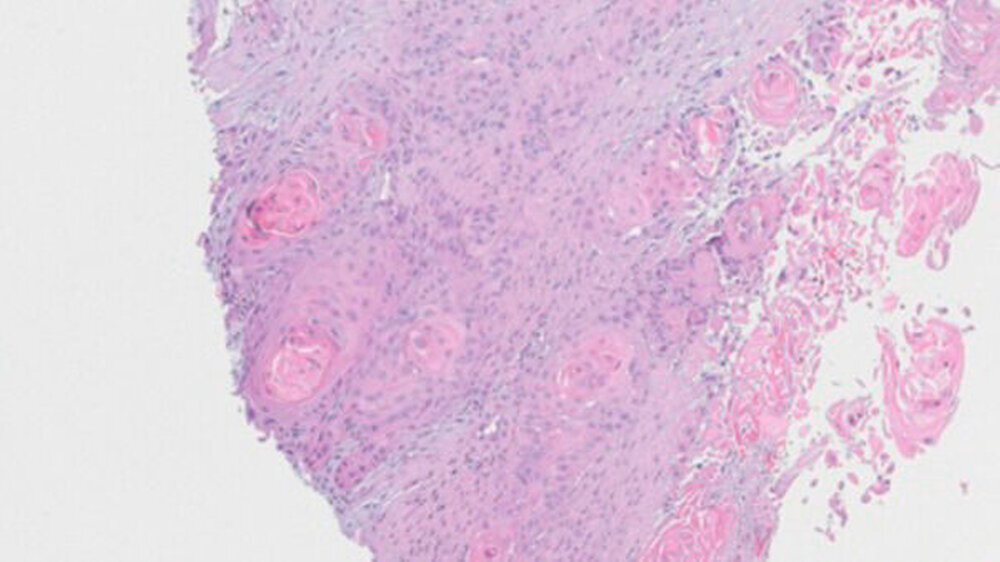

Weder das Röntgenbild noch die weitere Untersuchung mit magnetresonanztomografischer Bildgebung gaben eindeutigen Aufschluss. Daraufhin wurde eine Biopsie veranlasst, die die Verdachtsdiagnose einer Metastase des oralen Plattenepithelkarzinoms histologisch bestätigte.

Plattenepithelkarzinome sind von den Epithelien der Haut und der Schleimhäute ausgehende bösartige Tumoren, die häufig metastasieren über die abführenden Lymphgefäße in regionale oder weiter entfernt liegende Lymphknoten. Sie gelten als zweithäufigste bösartige Hauttumoren. Man geht von rund 70.000 Neuerkrankungen pro Jahr aus. Eine Streuung dieses Karzinoms über den Blutweg ist sehr selten, aber kann - wie in diesem Fall - sogar vom Mundboden bis in den Oberarm reichen.